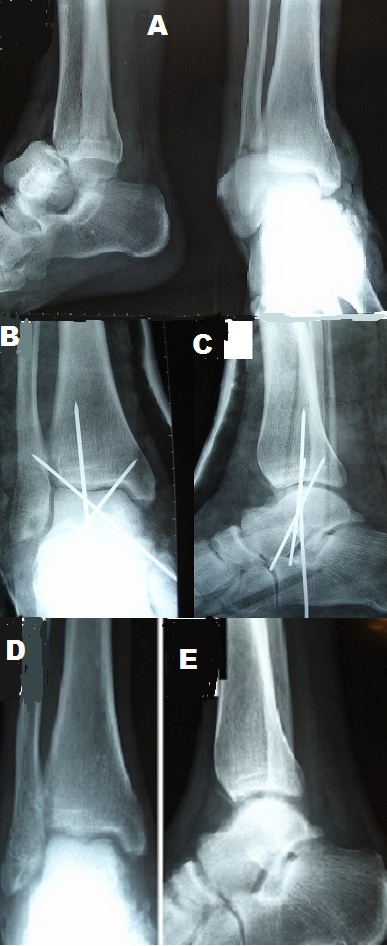

Enucleation or triple dislocation of the talus is a rare injury; in literature, it represents 2 to 10% of the talar trauma. The prognosis for this type of injury is dominated by the risk of osteonecrosis. We report a case of closed enucleation of the talus, treated in a conservative manner with satisfactory functional outcome. It's a patient of 32 years, victim of a road traffic accident that resulted in an injury of the right foot with pain and total functional impotence. The clinical examination showed a deformation of the foot in valgus, with a protruding talus in the anterolateral leads. The radiography of the ankle objectified anterolateral complete enucleation of the talus with a fracture of the non-displaced lateral malleolus (A). The reduction of the dislocated talus was made by external maneuver, and digital pressure after having set foot in supination and forced equine. The rear foot stability was maintained by a trans-calcaneofibular -talo-tibial pin and two Astragalus-tibial pin cross (B,C). The immobilization of the ankle and the foot was made by a cast boot for two months followed by Rehabilitation. The support has been authorized in the fourth month and the resumption of work in the seventh month after the accident. At 18 months of follow-up, the ankle was painless, stable with a satisfactory mobility. The standard X-rays of the ankle showed no abnormal bone or joint, or sign of necrosis (D, E).